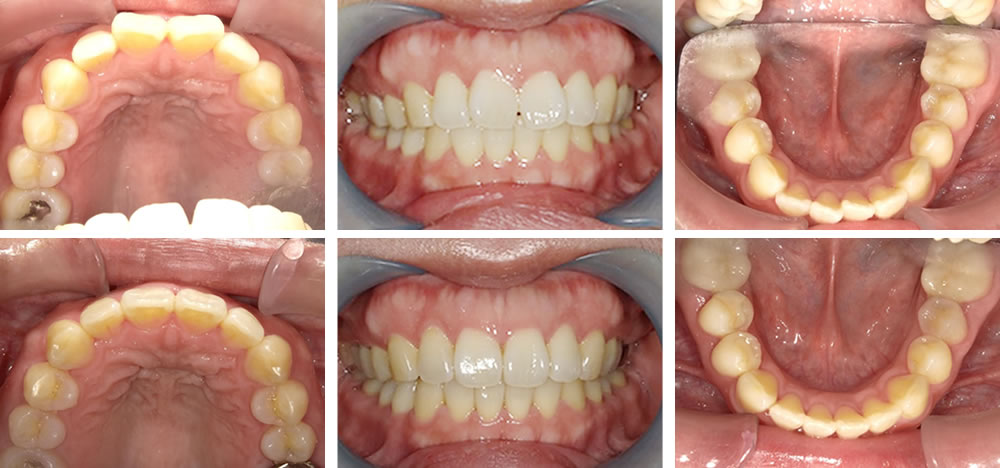

矯正治療